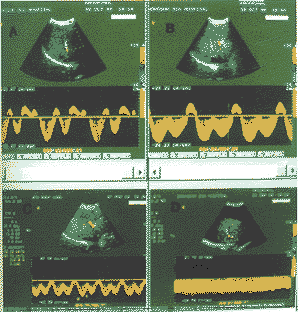

参考Bolondi方法〔2〕,将肝静脉多普勒频谱分为三种类型。①HV0:三相波或四相 波,即两个负向波,一个或两个正向波;②HV1:波幅减低且无反向血流;③HV2:连续平坦 波形,类似门静脉血流(图1)。另参考Bolondi及Arda等〔5〕方法将HV0波型定为 正常波型,HV1及HV2波型归为异常波型。

图1 A、B为HV0波型,C为HV1波型,D为HV2波型